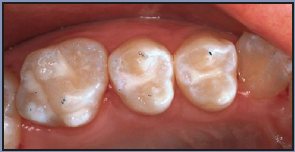

Once a decision has been made by the dentist to provide a preventive treatment, a sealant can be placed if the tooth is determined to be caries-free. The standard procedure of visual examination and radiographs typically used to make the determination is now being supplemented by new technologies such as fluorescence, transillumination, electrical conductance, and digital radiography.

One technological example is the Spectra (Air Techniques), (Figure 1) a device that uses laser fluorescence directed to the occlusal surfaces to determine demineralization and caries. This and other scientific advances benefit clinicians because, although studies have shown that sealing incipient decay will arrest it, frank occlusal decay should not be sealed, nor should primary teeth that are close to exfoliation.

Figure 1 - Example of Caries Detection Aid (Courtesy of Air Techniques)

Figure 1